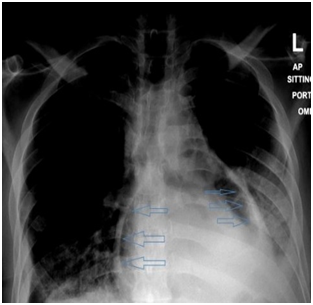

On initial examination, the patient was found to have borderline BP (SBP 101, DBP 60), diminished air entry at the bilateral right and left inferior lung fields. The cardiac examination was remarkable for normal S1, S2 and distended jugular venous distension of 10cm. Chest radiography (CXR) showed an intact esophageal stent along with radiolucent rim surrounding the cardiac silhouette (Figure 1). Echocardiogram (echo) revealed an air gap sign echoic dense space at the anterior and basal part of the heart consistent with the pneumopericardium with no signs of tamponade (Figure 2).  Computed tomography (CT) scan chest confirmed the presence of pneumopericardium in anterior pericardium along with left sided mediastinal pocket of air with foci of gas above the esophageal stent likely communicating with the pericardium (Figure 3). Given the clinical and radiological evidence of the symptomatic large pneumopericardium, we consented the patient on an emergency pericardiocentesis. Goals of care were discussed with the patient and his family and the patient opted interventional care measures. A following pericardiocentesis (with off label CT guidance) right sided parasternal approach (marked at the right 5th intercostal space with angulated entry projection of 70 degree medially with 27mm depth) was performed successfully with aspiration of 70ml of air followed with frothy blood-stained aspirate. The gentleman symptoms resolved immediately with picked up BP (SBP 123,DBP 67) and pigtail kept and secured in place for 5days without any complications.  Thereafter, a follow up echo and CT scan repeated and showed bright improvement in the clinical status (Figures 4 & 5) respectively.

Figure 1 (Sitting CXR showed radiolucent rim surrounding the cardiac silhouette).